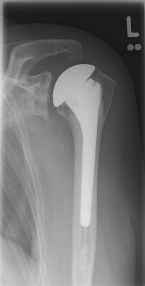

links: X-ray image of a cap prosthesis ("surface replacement")

right: cap prosthesis ("surface replacement", type "Durom" Fa. Zimmer)gkl